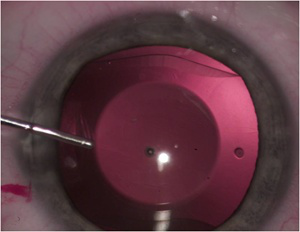

新しい近視治療 Icl 2 眼内への挿入動画 Youtube